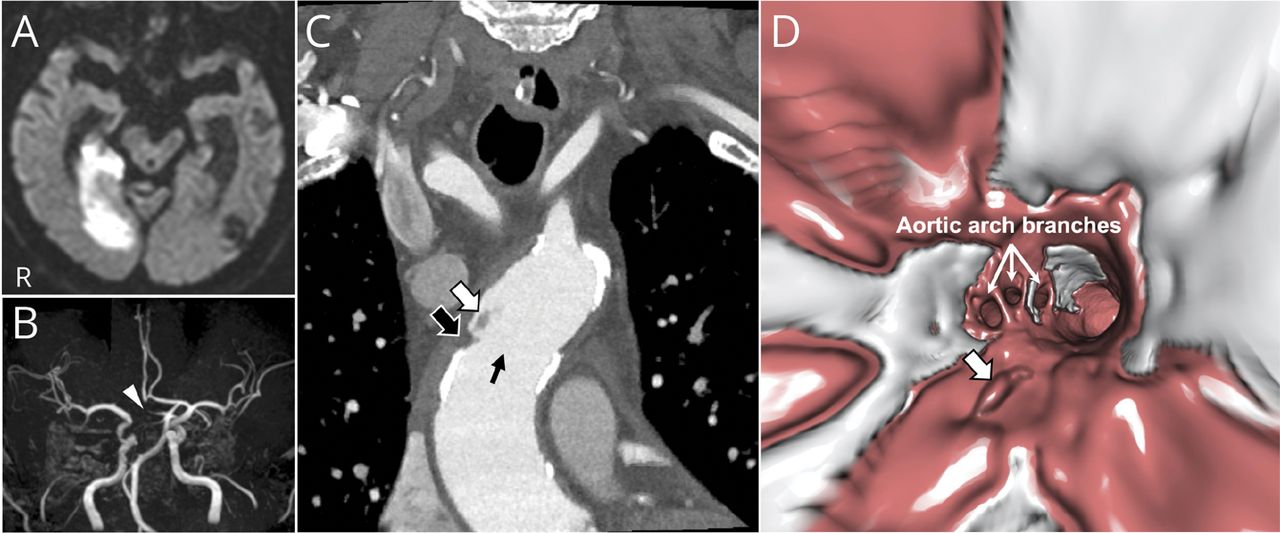

一个80岁的人开发了一个急性缺血性中风和右大脑后动脉(PCA)闭塞(图中,A和B)。心脏和颈动脉超声检查和24小时心电图监测没有确定任何栓子来源。ECG-gated 4 d CT血管造影(CTA)显示noncalcified斑叠加移动组件升主动脉(图中,C,视频1)。使用数据集从虚拟angioscopy ECG-gated 4 d CTA显示seaweed-like移动组件在三维视图中(图D,视频1)。这是诊断为aortogenic栓塞。华法林的抗凝治疗是由氯吡格雷国际标准化比率为2.0 - -3.0,和低密度脂蛋白胆固醇水平控制在低于70 mg / dL伐。

(一)41脑MRI diffusion-weighted成像序列显示了一个高强度信号正确的大脑后动脉(PCA)地区。(B) 41大脑磁共振血管造影序列显示正确的PCA闭塞(箭头)。(C)冠状的ECG-gated 4 d CT血管造影显示斑块(黑色箭头)附加组件(白色箭头)。(D)虚拟angioscopy从升主动脉的角度(C)的小箭头显示了附加组件(白色箭头)。

ECG-gated 4 d CT血管造影显示了移动组件摆动与脉动的流。虚拟angioscopy显示了seaweed-like移动组件的近端部分主动脉弓分支。下载补充视频1通过http://dx.doi.org/10.1212/012054_Video_1

主动脉斑块是不明原因引起的中风的原因之一。1ECG-gated 4 d CTA可以评估主动脉斑块流动性提升主动脉弓和整个主动脉弓。ECG-gated同步减少运动产物non-ECG-gated CT相比,提高了评估斑块形态和流动性。2此外,虚拟angioscopic看来,这是一个图像处理技术提供血管内腔的观点,3可以在3 d显示斑块流动性,使其容易理解斑块之间的位置关系和主动脉弓分支。